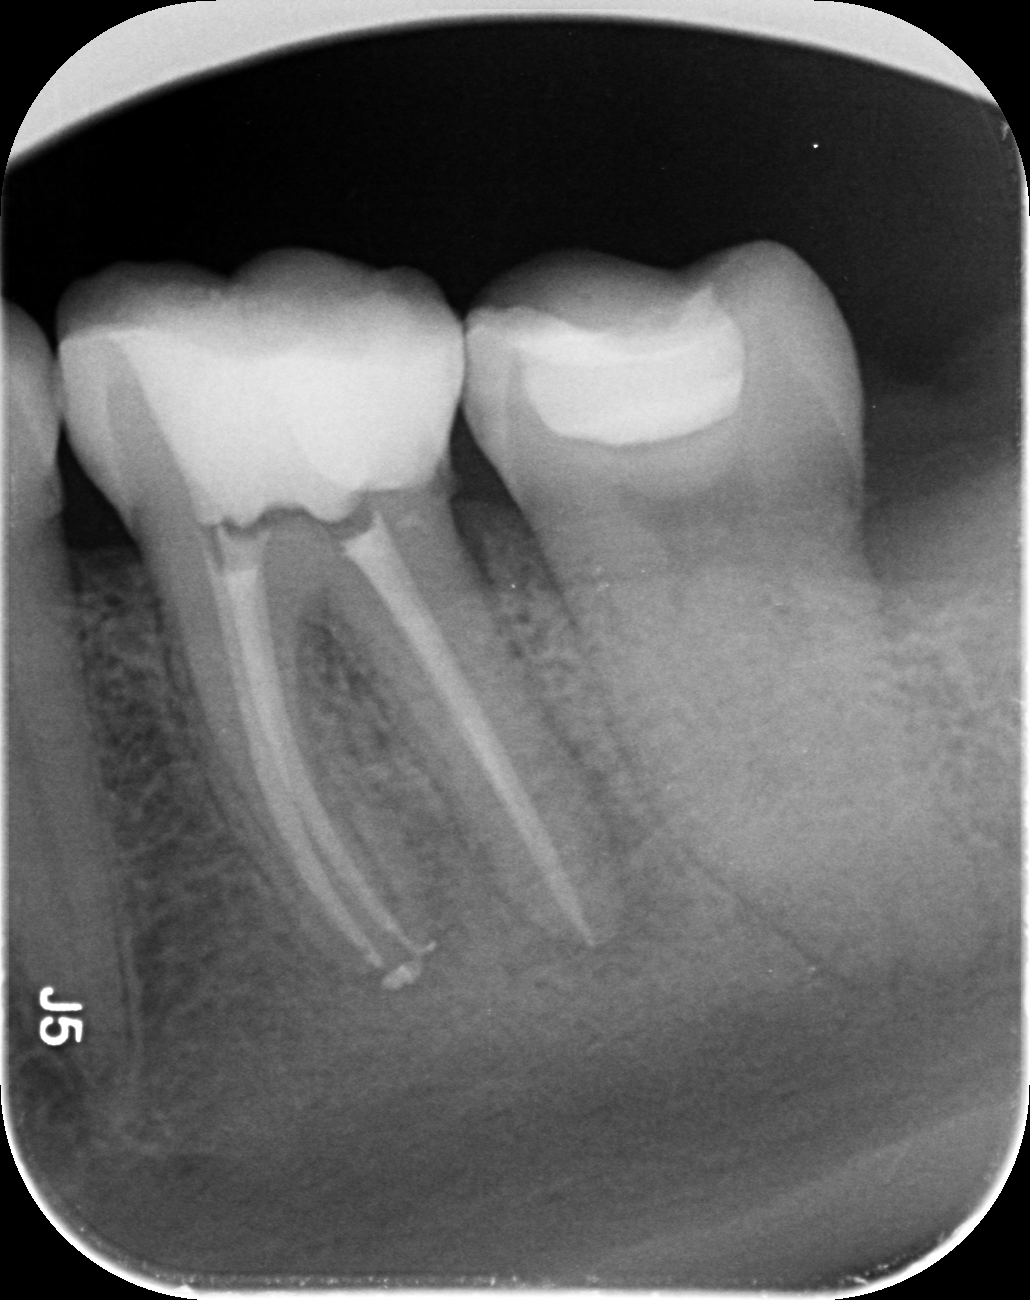

Dantų kanalų gydymas